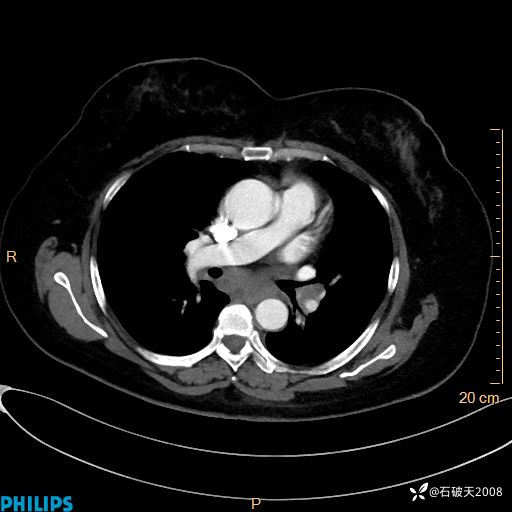

纵隔窗

静脉期